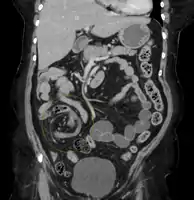

Coronal CT of the abdomen, demonstrating a volvulus as indicated by twisting of the bowel stock